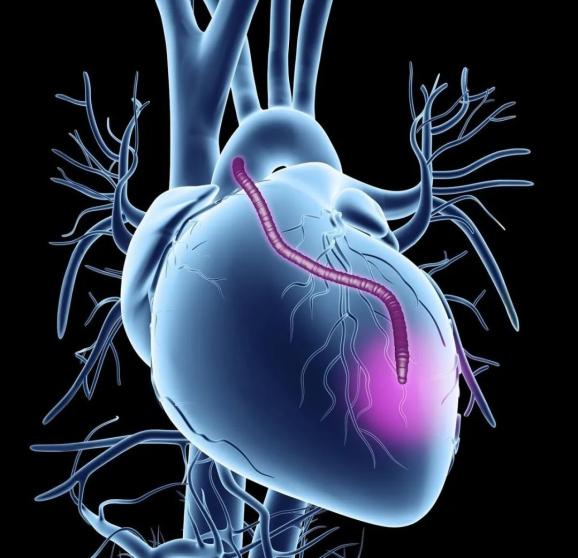

心脏是怎么固定的男子心肌梗死,检查血管没有狭窄,没有闭塞_https://www.jmylbn.com_新闻资讯_第4张痉挛导致的血管突然闭塞,这种心肌梗死并不是我们最常见的心肌梗死。我们最常见的心肌梗死是动脉粥样硬化,斑块加重,不稳定斑块破裂后,形成血栓,血栓堵塞心脏血管,最终发生了心肌梗死。

其根源在于动脉粥样硬化,也就是有些老百姓说的血管垃圾。形成的根源在于:遗传因素、抽烟酗酒、肥胖、久坐不运动、不健康饮食、熬夜、压力大、高血压、糖尿病、高脂血症等等。这些因素越多,越容易形成动脉粥样硬化,越容易加重斑块,最终形成冠心病,不稳定的斑块在寒冷、暴躁、抽烟、酗酒、剧烈运动等等等等刺激下就可能会发生破裂,形成血栓,发生心肌梗死。

这种心肌梗死的抢救方法就是溶栓或支架支架。